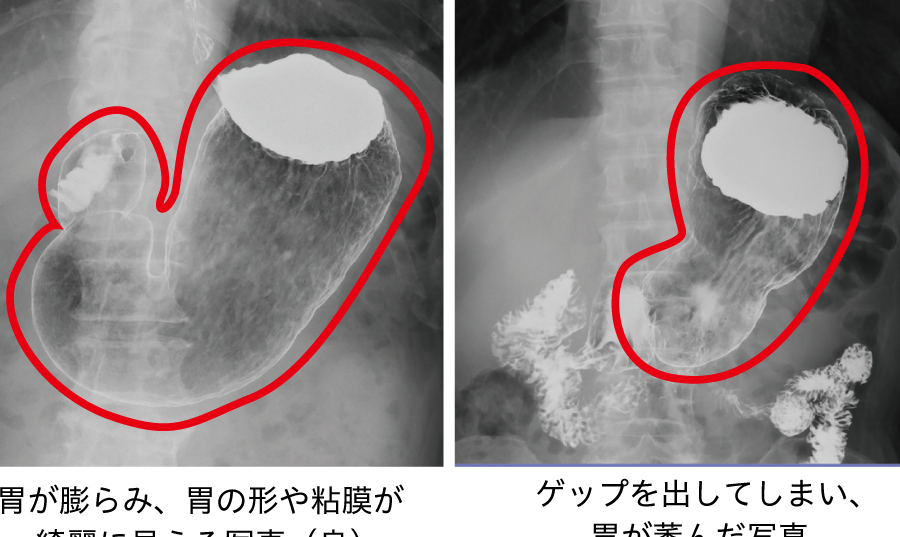

バリウム検査は、消化器系の状態を鮮明に映し出す重要な診断手段です。この検査では、バリウムという造影剤を使い、X線画像を取得します。バリウムは消化管を覆い、形状や異常をはっきりと確認できます。検査中、患者はさまざまな体位で画像を撮影されます。

- X線撮影: バリウムが消化管に広がった後、X線を用いて画像を撮影します。特定の体位(仰向け、横向きなど)をとることがあります。